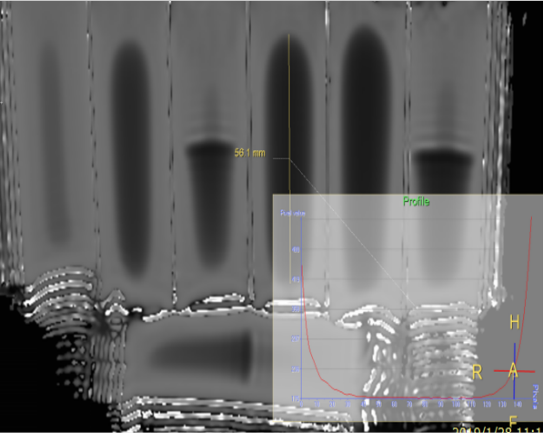

w材料伪影存在与否、类型、范围大小:根据材料,捕捉伪影特征

w材料实测漂移距离:磁体内实测距离